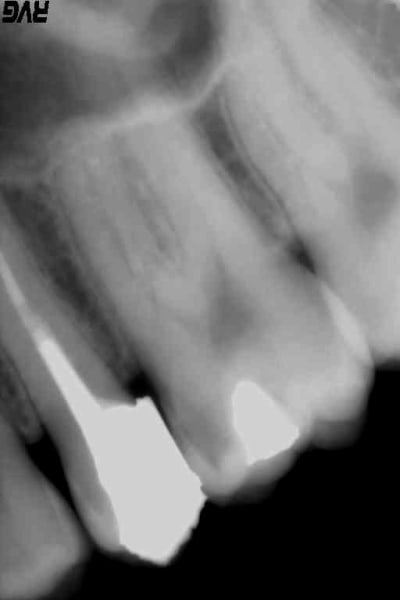

je suis étonné que personne n'ai dit qu'il n'y avait pas d'os entre les 2pm .

je dis ça je dis rien :-))))

donc je me dis que ce ne doit pas etre un cas facile , et elle a du le sentir la dentiste . d'où son discours mitigé ,peut être .

C'est un cas classique de PM , ni plus ni moins , elle a des gencives saines , sans saignement , sinon il y aurait longtemps qu'elle aurait sauté au plafond ! pas de saignement au traitement , rien nada . Si on devait mettre des réserves sur ce genre de dents nos RCP exploseraient parce que des comme ça on en voit tous les jours . J'ai retrouvé une radio de la 15 en 2009 , qualité mauvaise de la radio mais j'ai changé de capteur , de PC et je ne sais pas pourquoi mais les radios ont été enregistrées en tiff ... et en plus j'en ai perdu en cours de route ou mal indexées , j'en sais rien donc la voilà . Ca fera plaisir à carident ! 9 ans on a le temps de voir pour l'implant . ah oui pour les fouilles m... en 2009 ,1 ère consult de cette patiente ; c'est pas moi qui ai fait la reconstitution ni l'endo d'ailleurs ....ahhhh mais je vous vois venir : noooon !

R7 gbpxo0 - Eugenol

C est toi qui a fait l amalgame en mesial de 26 ??

C est un capteur taille 1+ ?

Oui c'est moi ! je sais ... ça repart ! personne n'est parfait mais vue la carie sur la 14 , ça doit y aller à coup de coca , je pense j'ai pas eu trop le temps d'en causer l'autre jour ... c'est le genre de carie à évolution très rapide ... parce qu'en 2013 j'ai rien vu non plus alors que je l'ai soignée de l'autre côté . Bref , heureusement que c'était un amg !!! (je savais qu'un gogo allait me faire le coup de la 26 ! ) mais rien de bien méchant non plus , ça va se gérer sans pb et avec 45€ la société ne s'en sort pas trop mal !

Je ne comprends pas du tout comment tu peux blâmer cette consœur alors que la dent a quelque chose de bizarre au niveau de la séparation VP : comme une résorption :))